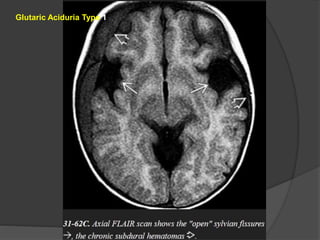

Glutaric Aciduria Type1 Imaging The three "signature" imaging findings of classic GA1 are (1)macrocrania, (2) bilateral widened ("open") sylvian fissures, and (3) bilaterally symmetric basal ganglia lesions. Severe GA1 may also cause diffuse hemispheric WM abnormalities. GA1 infants in metabolic crisis often present with acute striatal necrosis. Bilateral diffusely swollen basal ganglia that are T2/FLAIR hyperintense and that restrict on DWI are typical.

Chronic GA1 causesenlarged CSF spaces and atrophy. The volume loss may tear bridging veins that cross from the brain surface to the dura, resulting in recurrent subdural hematomas. GA1 does not enhance on T1 C+ scans. MRS is nonspecific with decreased NAA, increased Cho:Cr ratio, and (during crisis) elevated lactate level. Glutaric aciduria type 2 (GA2) Imaging studies show symmetric T2/FLAIR hyperintensity in the basal ganglia and hemispheric WM, but the "open" sylvian fissures characteristic of GA1 are absent.